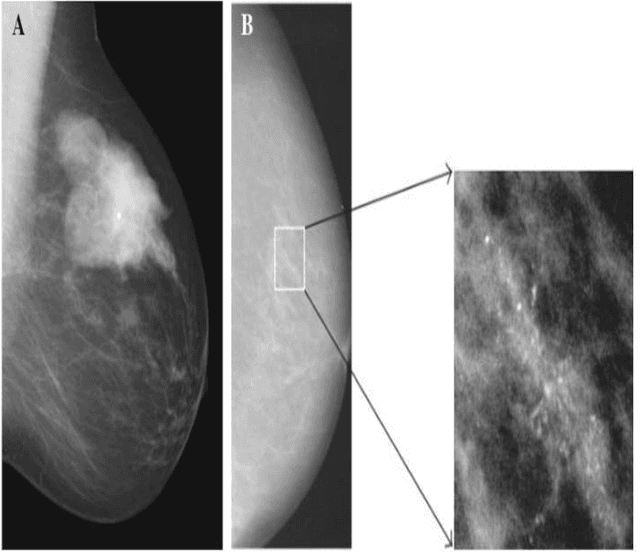

Abstract:Breast cancer is a common fatal disease for women. Early diagnosis and detection is necessary in order to improve the prognosis of breast cancer affected people. For predicting breast cancer, several automated systems are already developed using different medical imaging modalities. This paper provides a systematic review of the literature on artificial neural network (ANN) based models for the diagnosis of breast cancer via mammography. The advantages and limitations of different ANN models including spiking neural network (SNN), deep belief network (DBN), convolutional neural network (CNN), multilayer neural network (MLNN), stacked autoencoders (SAE), and stacked de-noising autoencoders (SDAE) are described in this review. The review also shows that the studies related to breast cancer detection applied different deep learning models to a number of publicly available datasets. For comparing the performance of the models, different metrics such as accuracy, precision, recall, etc. were used in the existing studies. It is found that the best performance was achieved by residual neural network (ResNet)-50 and ResNet-101 models of CNN algorithm.

Abstract:Breast cancer is a common cancer for women. Early detection of breast cancer can considerably increase the survival rate of women. This paper mainly focuses on transfer learning process to detect breast cancer. Modified VGG (MVGG), residual network, mobile network is proposed and implemented in this paper. DDSM dataset is used in this paper. Experimental results show that our proposed hybrid transfers learning model (Fusion of MVGG16 and ImageNet) provides an accuracy of 88.3% where the number of epoch is 15. On the other hand, only modified VGG 16 architecture (MVGG 16) provides an accuracy 80.8% and MobileNet provides an accuracy of 77.2%. So, it is clearly stated that the proposed hybrid pre-trained network outperforms well compared to single architecture. This architecture can be considered as an effective tool for the radiologists in order to reduce the false negative and false positive rate. Therefore, the efficiency of mammography analysis will be improved.